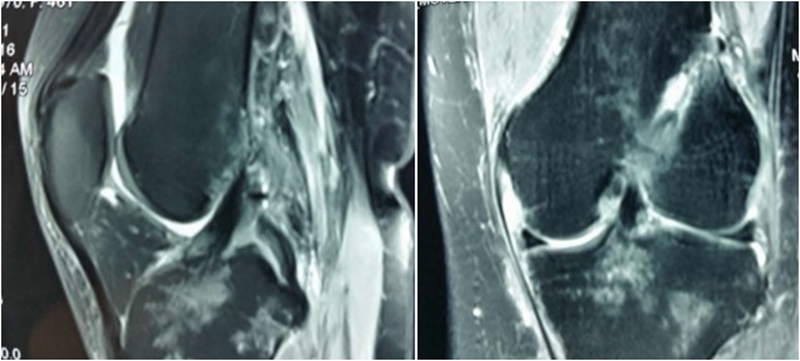

术前MRI

术后MRI